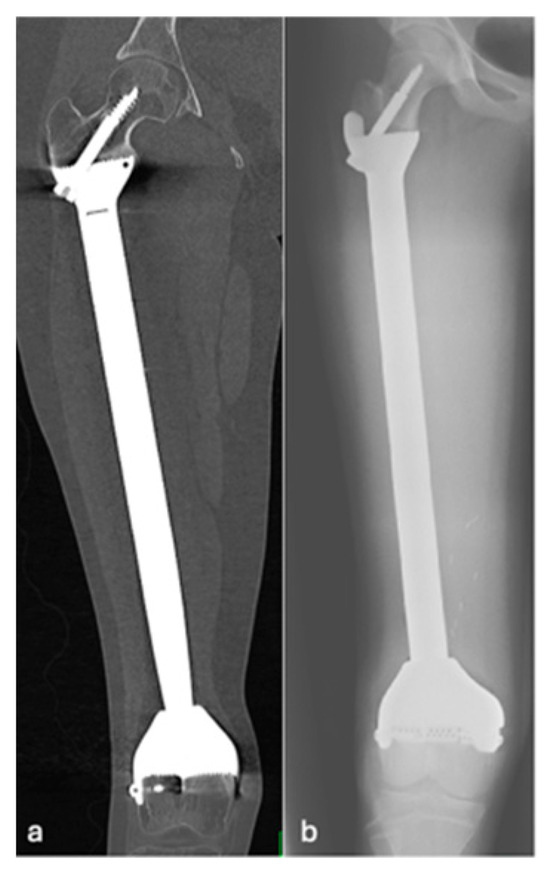

| Grade of loosening | |

| Grade 2 | 5 (17.9) |

| Grade 3 | 16 (57.1) |

| Grade 4 | 2 (7.1) |

| Grade 5 | 1 (3.6) |

| Grade 6 | 4 (14.3) |